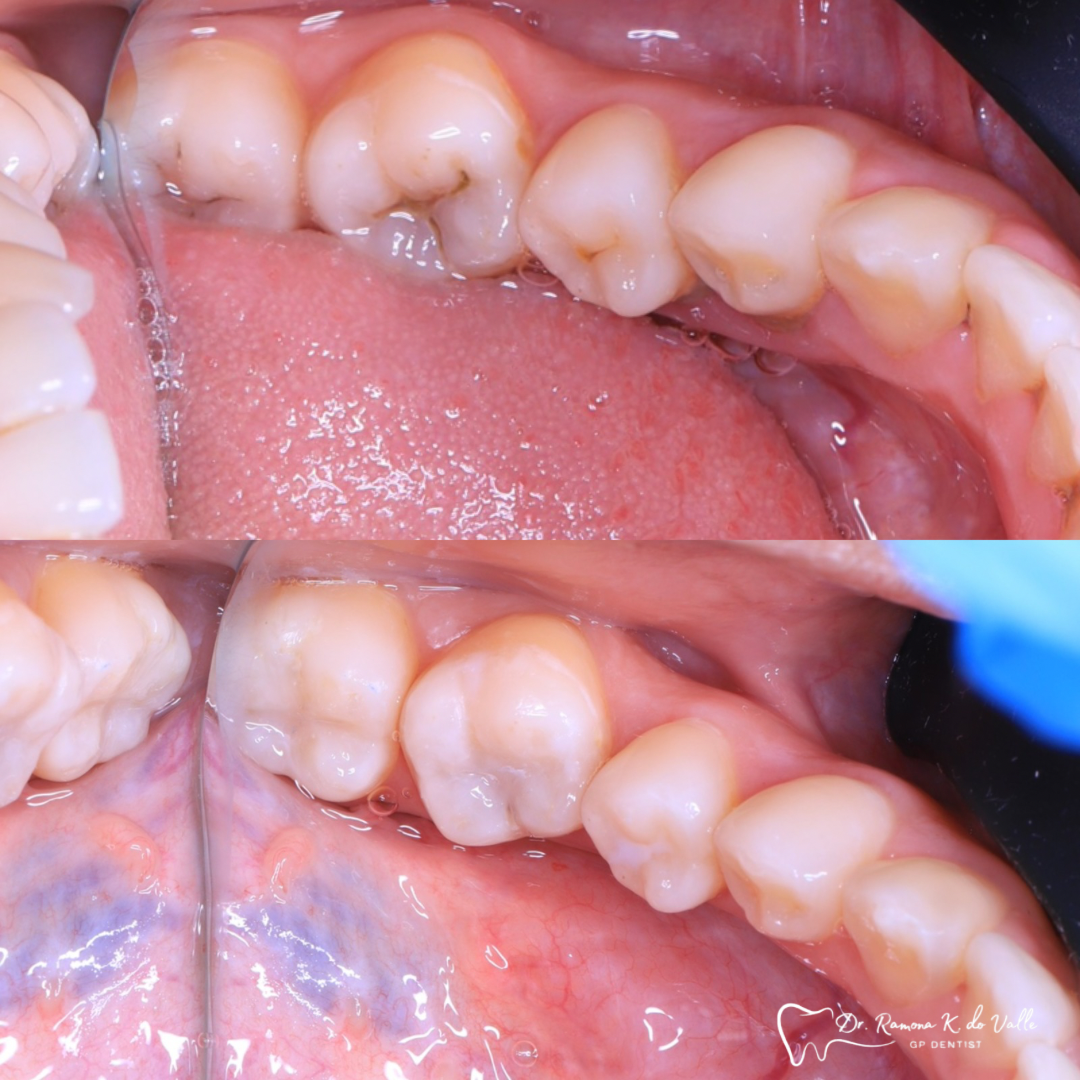

We remove weakened or decayed tissue and clean the area thoroughly. The goal is to preserve as much healthy structure as possible.

3. Layering the Composite Resin

The tooth-coloured resin is applied in thin layers and shaped carefully to match natural anatomy. For front-tooth work, we may combine several shades for a lifelike result.

5. Final Polishing and Bite Adjustment

We contour and polish the surface to a high gloss and ensure your bite feels natural in all positions.